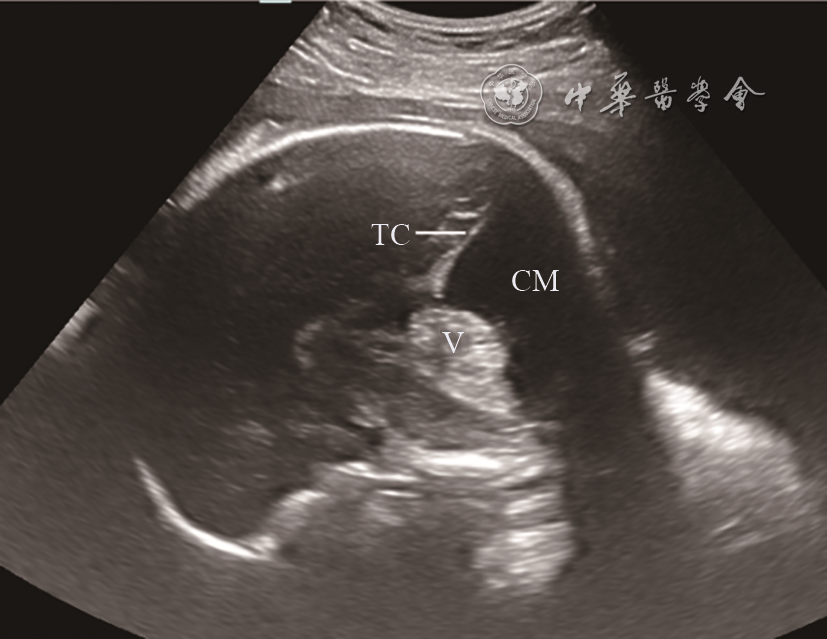

图5 胎儿后颅窝蛛网膜囊肿超声声像图(孕33周)。颅脑正中矢状面:小脑延髓池明显增大,小脑蚓部完整,受压前移,小脑幕上抬

注:V为小脑蚓部,TC为小脑幕,CM为小脑延髓池